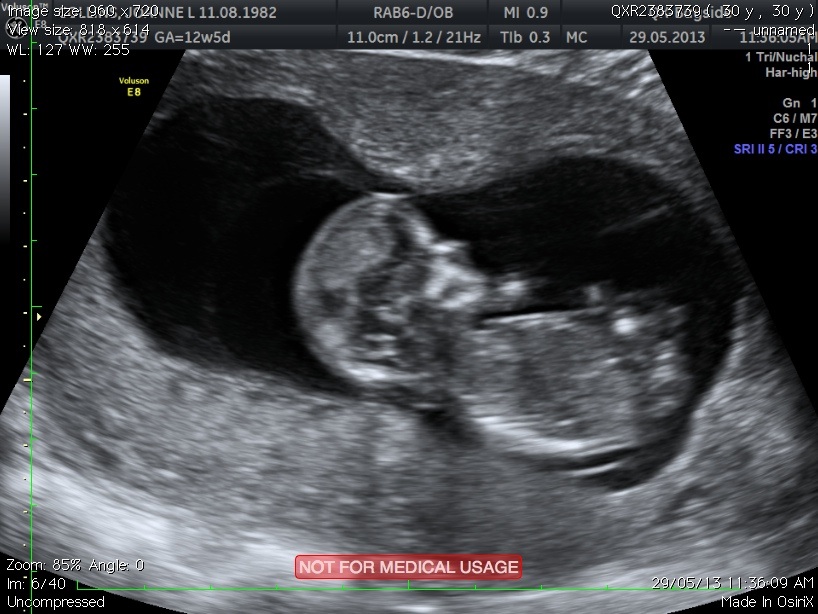

Hi, can anyone see a nub in this pic please? 12w5d. Thank you

Is there a nub in this pic please?

I'm not too sure the nub is clear enough to make a guess.....but it if I had to say one or the other, I would MAYBE lean towards boy.....congrats on a beautiful bubba

Any guesses on the skull please ladies?

I think there is a nub. But I am far from an expert. I am leaning boy on all regards.